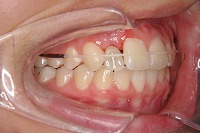

反対咬合を主訴に来院された、右側唇顎裂の10歳6ヵ月の女の子です。診断「右側唇顎口蓋裂で反対咬合を伴う」1期治療で反対咬合の解消と上顎の前歯の並びを修正しました。2期治療は抜歯をせず治療を行いました。